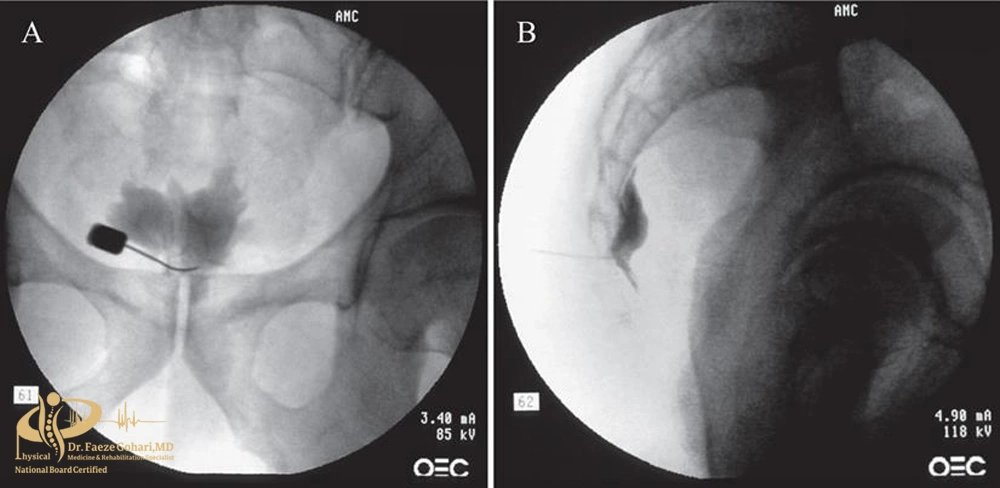

بلوک عصبی لگن و دنبالچه

در تصویربرداری زنده هنگام بلوک عصبی دنبالچه میتوان محل ورود سوزن و تزریق ماده بیحسی و بلاککننده عصب را مشاهده کنید.

بلوک عصبی لگن و دنبالچه روشی کمتهاجمی است که با تزریق داروی بیحسی (معمولاً همراه با کورتون) اطراف اعصاب هدف انجام میشود تا انتقال پیام درد به نخاع و مغز قطع یا کاهش یابد. این کار معمولاً تحت هدایت تصویربرداری (فلوروسکوپی یا سونوگرافی) صورت میگیرد تا ایمنی و دقت بالا برود.

- تعیین مسیر ورود سوزن: پزشک با کمک فلوروسکوپی (اشعه ایکس زنده) یا سونوگرافی مسیر ایمن برای رسیدن به اعصاب لگن یا دنبالچه را مشخص میکند.

- کنترل ایمنی: پیش از تزریق دارو، پزشک با کشیدن پیستون سرنگ (آسپیراسیون) مطمئن میشود سوزن داخل رگ قرار نگرفته است. در برخی موارد مقدار کمی ماده حاجب تزریق میشود تا محل دقیق پخش دارو تأیید گردد.